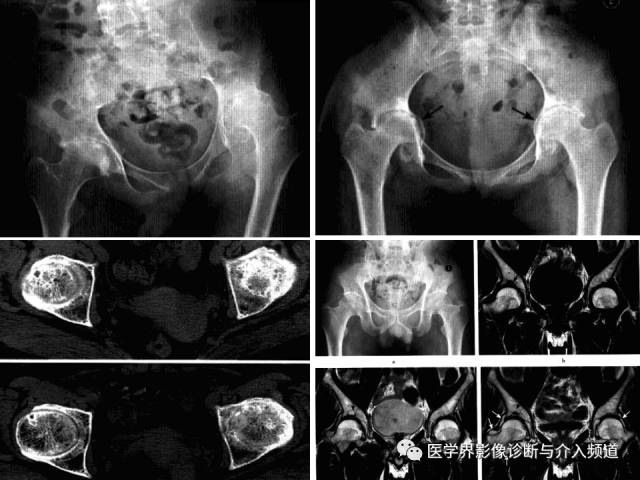

Charcot髋关节病

Charcot髋关节病,又称夏科关节、神经营养性髋关节病,是在中枢性或周围神经性疾病所致的髋关节深部感觉障碍基础上,因反复多次关节外伤继发引起的髋关节病变。常见原因多见于脊髓痨和脊髓空洞症,麻风、糖尿病、周围神经损伤、脊䯝肿瘤等疾病也可伴发。

病理:髋关节保护性感觉丧失,关节多次损伤后迅速退变、破坏,软骨剥落进入关节腔,软骨下骨硬化、碎裂;关节囊和韧带松驰,关节脱位,骨折修复性改变。

临床表现:病程长,多单侧受累,有外伤诱因,关节肿大,疼痛不明显,痛觉消失,深反射消失。

影像诊断:首先X线平片。

1、平片:早期关节内积液、软组织肿胀、关节间隙增宽;进展期股骨头关节面变平、关节内游离体,关节旁钙化及骨化,关节脱位;晚期骨端破坏、大量骨赘形成,反应性骨膜增生。

2、CT:早期髋关节积液,周围软组织水肿;随病情进展,骨端增生硬化,边缘骨赘形成,游离体;后期,骨端崩解,关节正常结构破坏,关节腔大量坏死骨块和钙化的软骨碎屑,周围软组织骨化、钙化,增强显示关节囊及滑膜囊明显强化、呈绒毛状突向关节腔。

3、MRI:早期关节积液,软骨变性、破坏,继而关节软骨碎裂、形成游离体,软骨下骨增生硬化、骨赘形成;最终骨赘断裂、骨端碎裂、关节结构消失,骨残端无明显水肿和骨髓浸润征象。增强显示关节囊及滑膜囊明显强化、呈绒毛状突向关节腔,骨残端无明显强化。

快速破坏性髋关节病

是一种不知确切病因而侵犯股骨头及髋臼导致髋关节在短时间内快速破坏的髋关节疾病。

病理:股骨头变小,负重区扁平,关节面软骨消失,软骨下骨破坏、碎片状骨坏死,骨小梁硬化、增粗。

临床表现:多发生于60岁以上老年女性,多一侧发病,无明显原因髋关节疼痛,之后逐渐加重,后期出现功能受限和跛行。

影像诊断:首选X线平片,髋关节正位及蛙氏位。

1、平片:髋关节间隙进行性消失是本病特征;早期股骨头无明显变化,数月间股骨头上方进展性破坏吸收,股骨头变扁,无囊变,骨赘增生不显著,周围软组织无明显异常。

2、CT:股骨头负重区骨质溶骨样改变,骨质碎裂的,关节面软骨大片状剥脱和皲裂,头中心骨质呈小圆形颗粒状改变,软骨下骨的连续性破坏,头外形不规则缺损,碎骨片线状分离。

3、MRI:股骨头及髋臼骨质吸收伴软骨丢失,股骨头向上外方移位,关节内积液,骨髓未见明显异常。